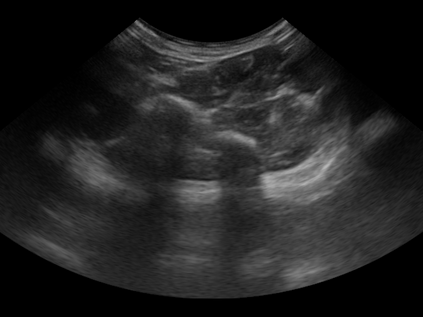

Three-dimensional (3D) freehand ultrasound (US) reconstruction without a tracker can be advantageous over its two-dimensional or tracked counterparts in many clinical applications. In this paper, we propose to estimate 3D spatial transformation between US frames from both past and future 2D images, using feed-forward and recurrent neural networks (RNNs). With the temporally available frames, a further multi-task learning algorithm is proposed to utilise a large number of auxiliary transformation-predicting tasks between them. Using more than 40,000 US frames acquired from 228 scans on 38 forearms of 19 volunteers in a volunteer study, the hold-out test performance is quantified by frame prediction accuracy, volume reconstruction overlap, accumulated tracking error and final drift, based on ground-truth from an optical tracker. The results show the importance of modelling the temporal-spatially correlated input frames as well as output transformations, with further improvement owing to additional past and/or future frames. The best performing model was associated with predicting transformation between moderately-spaced frames, with an interval of less than ten frames at 20 frames per second (fps). Little benefit was observed by adding frames more than one second away from the predicted transformation, with or without LSTM-based RNNs. Interestingly, with the proposed approach, explicit within-sequence loss that encourages consistency in composing transformations or minimises accumulated error may no longer be required. The implementation code and volunteer data will be made publicly available ensuring reproducibility and further research.